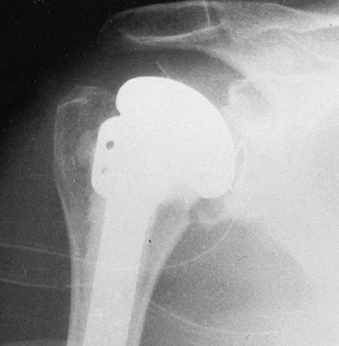

Take final radiographs to document the position of the prosthesis (Fig. 101.46).

Figure 101.46. Radiographic appearance of the total shoulder arthroplasty.